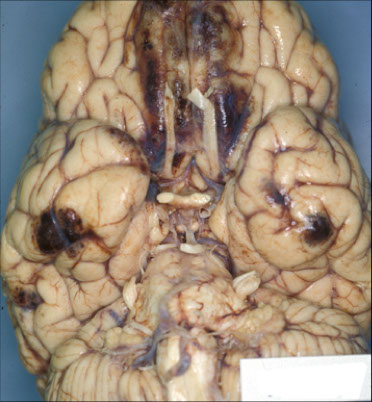

Cerebral contusion in fixed brain

Contrecoup or “gliding” contusions of the medial aspects of the orbital gyri and ventral surfaces of the temporal lobes in man who fell and hit the back of his head.